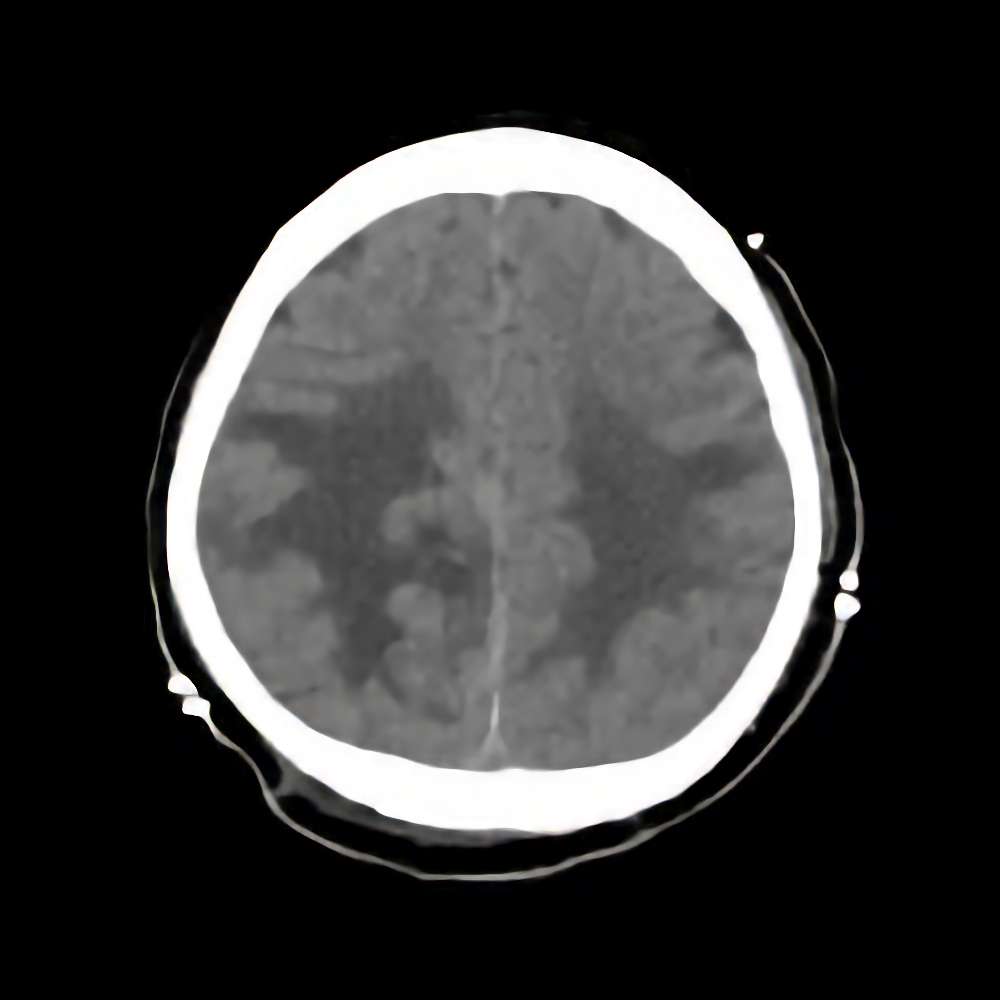

症例 '14年11月

No.

※ 画像をクリックすると拡大表示します。症例No.は平成29年から起算しています。

年_番号

手術年月

患者年齢

’14_169

'14年11月

60代

病名

術式

備考

傍矢状洞髄膜腫

断層撮影

手術前

1

手術前2

手術後